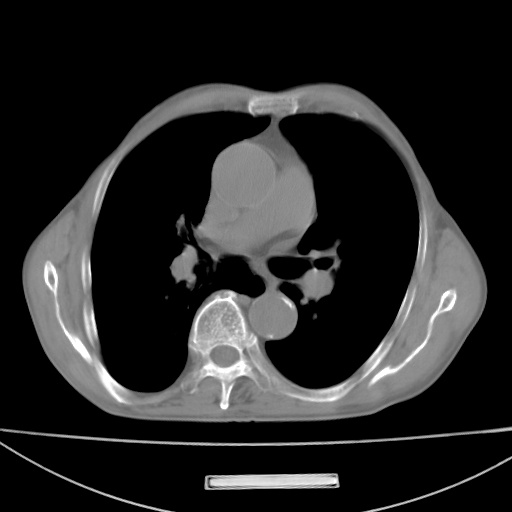

标题: CT13796:请会诊右上费病变!

患者男80岁,反复咳嗽多年,咳喘伴咯血1月

右上肺周围型肺癌伴肺门、纵膈淋巴结转移

考虑为:右肺上叶肺癌伴阻塞性肺炎、右肺门及纵膈淋巴结转移。